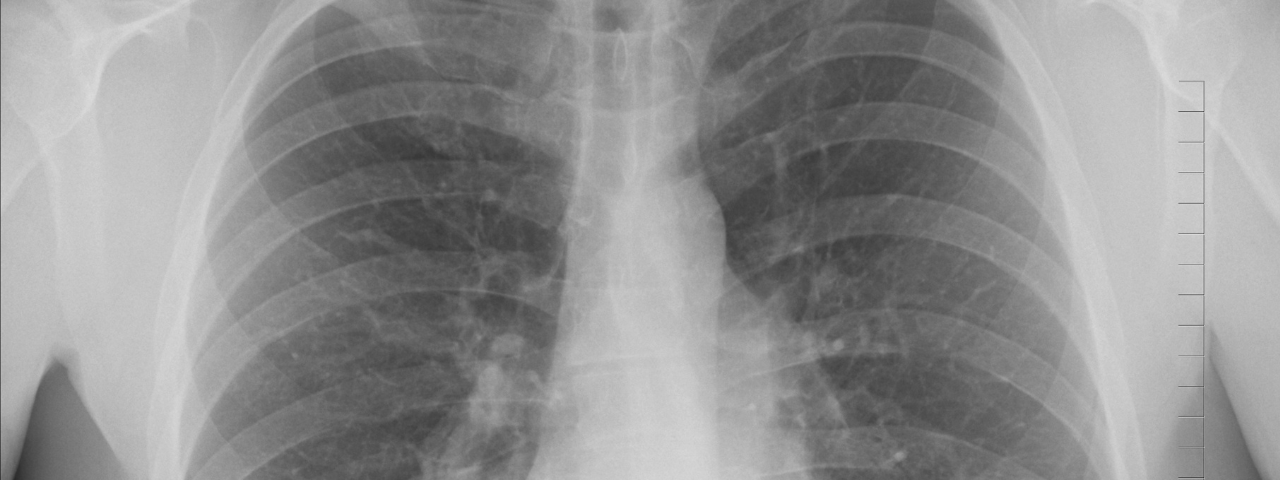

Lung Cancer Screening

Lung Cancer Screening helps find problems early, usually before you notice anything is wrong and at a stage when treatment could be simpler and more successful. Lung cancer often has no symptoms in its early stages, which can lead to late diagnosis. Most lung cancers grow slowly enough to be detected early through screening.

- If you are identified as someone who has a higher chance of developing lung cancer you will be invited to have a CT scan. This checks for early signs of lung cancer. CT scans will take place at Royal Berkshire Hospital and take only a few minutes to complete.